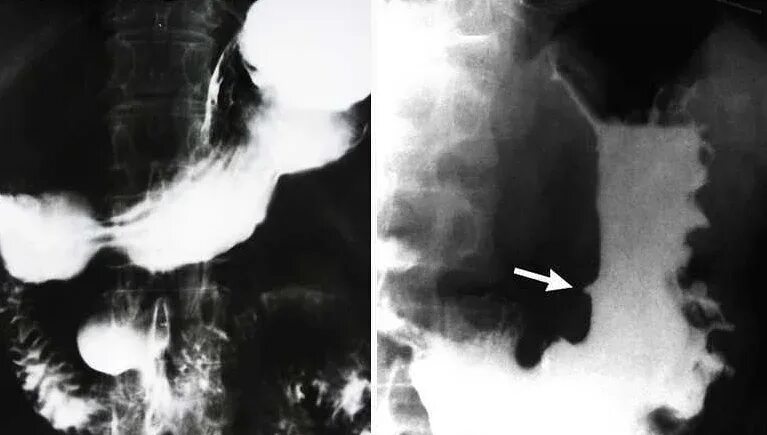

Перфоративная язва желудка рентген. скопия желудка рентген. язвенная болезнь двенадцатиперстной кишки рентген.

Рентген желудка с барием язва. рентгеноскопия желудка норма. контрастирование желудка рентген. рентгеноскопия желудка с барием язва желудка.

Скопия желудка рентген. контрастирование желудка рентген. рентген двенадцатиперстной кишки. рентген изъязвления в желудке.